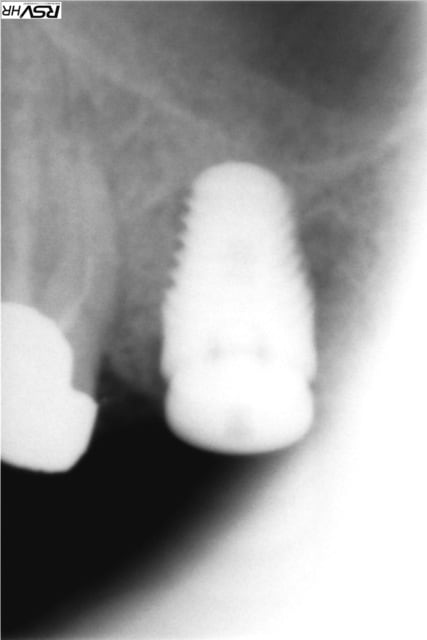

même si je me redirige plutôt vers Zimmer avec une insertion primaire supérieur (à mon avis ) voici un cas de plusieurs années

j'avais gardé une racine distale de 46 (montage 2 ccm soudées au début 4647- avec diastème avec 45 ;2008;le montage

n'a pas tenu longtemps=extraction racine distale et

implantation immédiate legacy2 7 mm(2011)

et ccm transvissée 3 mois après

radio à 2015